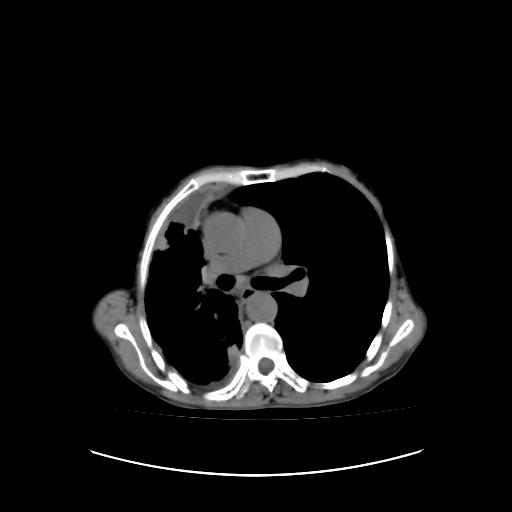

可见多发肺内病灶,且胸膜病灶较多有圆球状而非丘状,多考虑胸膜转移瘤伴胸腔积液,右侧胸廓缩小固定,且部分病灶呈丘状,尚不除外恶性胸膜间皮瘤伴肺内转移

右侧胸膜增厚,局部呈结节状增厚,右侧胸腔少量积液。双肺未见确切肿块影。纵隔未见淋巴结肿大。气管、支气管通畅。考虑右侧胸膜间皮瘤(恶性?)可能性大。不除外癌性胸膜炎。

恶性胸膜间皮瘤伴肺内转移可能性大;或胸膜、肺内均为转移瘤,左肺下叶亦见多发小结节影。

右侧胸廓塌陷,右侧胸膜广泛增厚并见多发胸膜结节,右侧少量胸腔积液并包裹。

右侧广泛胸膜增厚,局部呈结节状增厚,右侧胸腔少量积液。双肺未见确切肿块影。纵隔未见淋巴结肿大。气管、支气管通畅。考虑右侧胸膜间皮瘤(恶性?)可能性大。支持!

右胸腔结节均考虑来自胸膜(部分来源于叶裂),考虑胸膜间皮瘤或转移瘤.